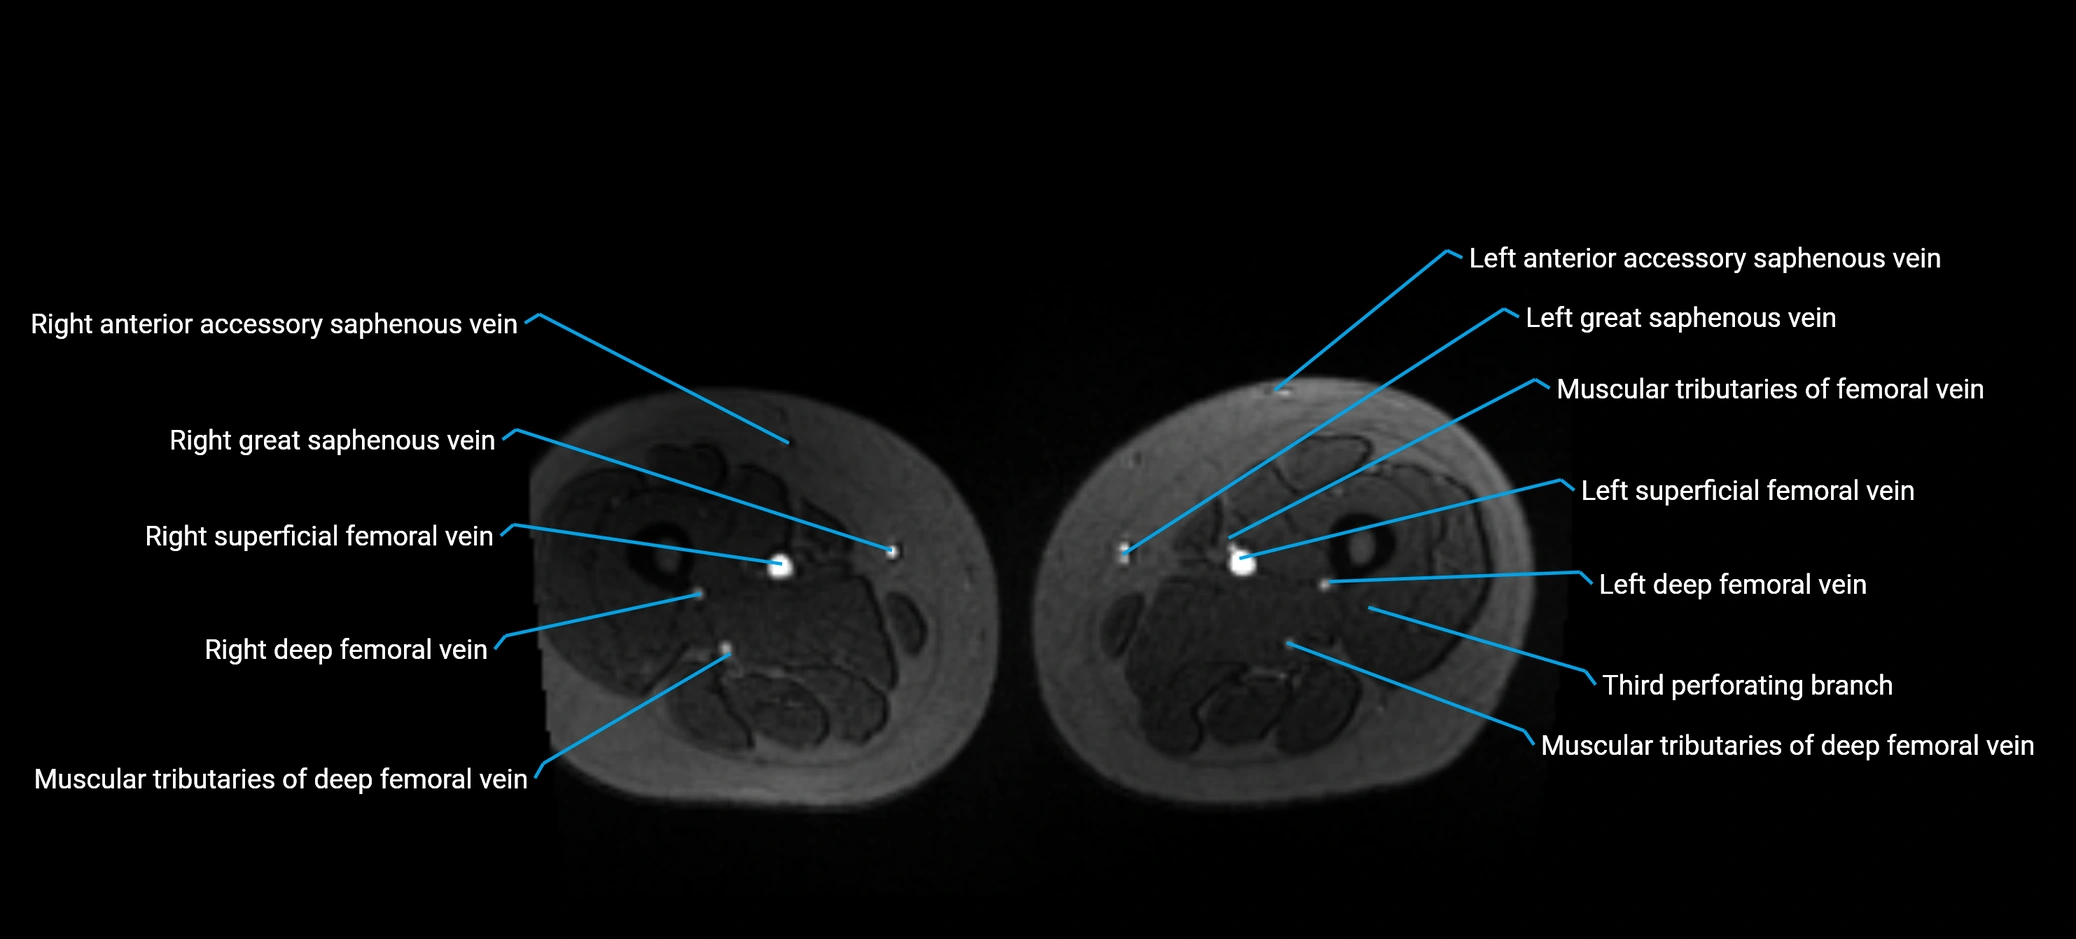

MRI image

image